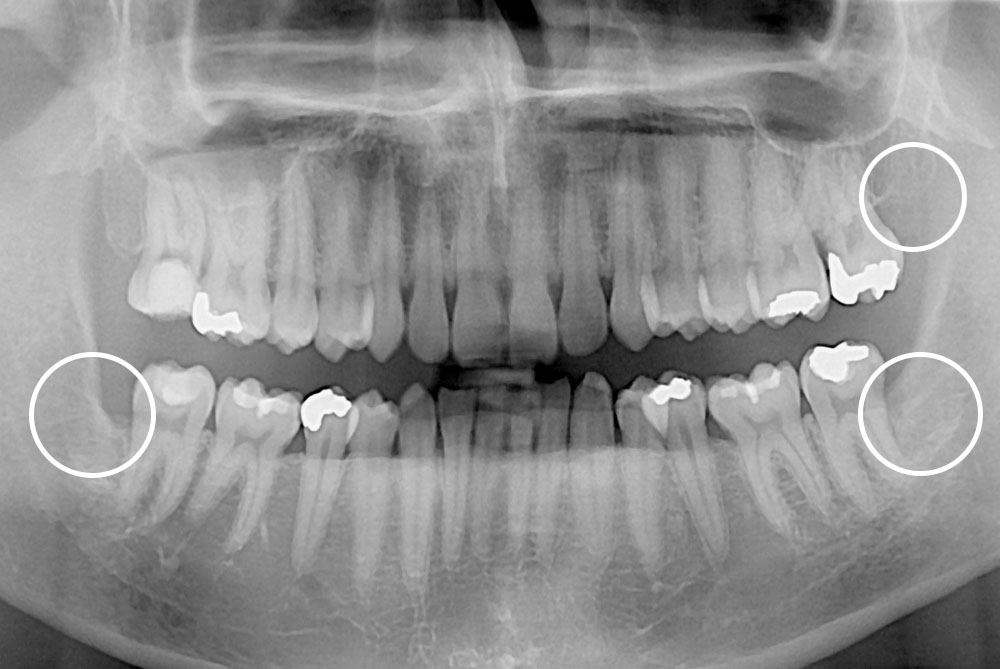

치료후 : 2020-02-10

세종치과는 구강악안면외과학 박사이신 원장님이 발치하는 치과입니다.